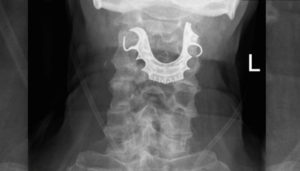

அந்த எக்ஸ்ரேவில் தொண்டை குழியில் பெரிய பல் செட் எலும்புகளுக்கு நடுவே மாட்டி இருந்துள்ளது. இது குறித்து முதியவரிடம் விசாரித்துள்ளனர். அப்போது அவர் கூறுகையில், ‘ஒரு வாரத்துக்கு முன்பாக எனக்கு தொண்டையில் அறுவை சிகிச்சை நடந்தது. அப்போது மருத்துவர்கள் தவறுதலாக இப்படி செய்து விட்டனர் என நினைக்கிறேன்’ என கூறியுள்ளார்.